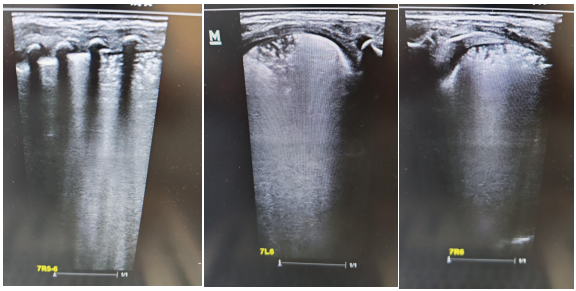

術前肺部超聲及CT均提示雙肺實變明顯

面對挑戰(zhàn),新生兒科迅速啟動多學科會診(MDT),聯(lián)合呼吸內科、兒童呼吸科、中心試驗室等科室專家深入討論。在充分與家長溝通并取得同意后,醫(yī)療團隊成功為患兒實施了本市首例新生兒纖維支氣管鏡和肺泡灌洗術,同時取灌洗液進行 NGS檢查、明確病原學診斷,團隊快速調整個性化診療方案,精準調控參數(shù)、嚴密監(jiān)測病情,穩(wěn)步推進階梯式撤機脫氧,全力攻克救治難關。